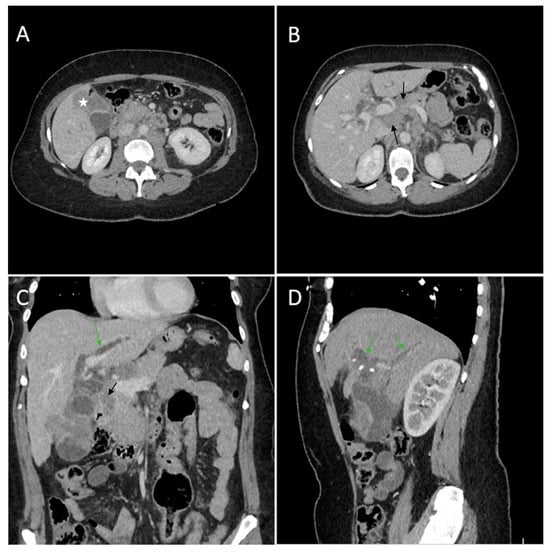

Figure 6. Multiplanar sections of contrast-enhanced CT acquisitions richly illustrating gallbladder carcinoma with an associated necrotizing infectious component. (A,B). Distended gallbladder with asymmetrical thick-walled gallbladder (16 mm) (white arrow). (C,D). Abscess adjacent to the gallbladder (black arrow); extension to the duodenum (blue arrow).

A 69-year-old female patient with a past medical history of diabetes type II presented to the Emergency Department with a 2-day upper abdominal pain, accompanied by hypotension and oligoanuria. Routine laboratory evaluation showed elevated inflammatory markers (leukocytosis, procalcitonin 100 ng/mL, CRP 126 mg/L), elevated transaminases and ferritin. The patient underwent contrast-enhanced computed tomography (Figure 6). CT images depicted a distended gallbladder (99 mm in longitudinal measurement), with asymmetrical thick-walled gallbladder (16 mm), heterogeneous contrast enhancement (Panel A), with a gallbladder neck stone (10 mm), extended to the duodenum (Panel B and Panel C). CT showed multiple low-attenuation hepatic masses with peripheral enhancement, adjacent to the gallbladder fossa (segment V) and intrahepatic biliary tract dilatation. Below the liver and adjacent to the gallbladder fundus, fat standing and free fluid were observed. These imaging findings were suggestive of acute cholecystitis complicated by an intrahepatic abscess or gallbladder carcinoma with wall perforation into the adjacent liver.